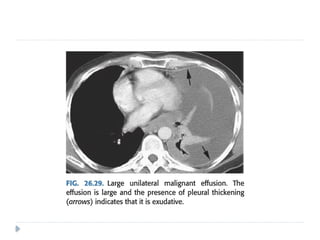

 Malignant pleural effusions are also exudates

although malignant cells may not always be detected

on cytologic evaluation.

 CT scanning is excellent at detecting small amounts of

fluid and is also often able to identify the underlying

intrathoracic causes (e.g. malignant pleural deposits or

primary lung neoplasms) as well as subdiaphragmatic

diseases (e.g. subdiaphragmatic abscess).

 CT is not able to differentiate between a transudative

or exudative pleural effusion with similar fluid densities

and non-differentiating rates of loculation and pleural

thickening

 However, CT can help distinguish between pleural

effusion and pleural empyema

 Empyemas usually:

 form an obtuse angle with the chest wall

 unilateral or markedly asymmetric whereas pleural effusions

usually bilateral and similar in size .

 Biconvex , whereas pleural effusions are concave in shape

towards the lung.

 Features suggestive of an empyema on CT include:

 Enhancing thickened pleura ( split pleura sign) whereas

pleural effusion has thin imperceptible pleural surfaces

 locules of gas absent unless recent thoracocentesis

 Obvious septations

 Associated consolidation

 Associated adjacent infection (e.g. subdiaphragmatic abscess)

 CT scanningis excellent at detecting small amounts of fluid and is also often able to identify the underlying intrathoracic causes (e.g. malignant pleural deposits or primary lung neoplasms) as well as subdiaphragmatic diseases (e.g. subdiaphragmatic abscess).  CT is not able to differentiate between a transudative or exudative pleural effusion with similar fluid densities and non-differentiating rates of loculation and pleural thickening  However, CT can help distinguish between pleural effusion and pleural empyema

 Empyemas usually: form an obtuse angle with the chest wall  unilateral or markedly asymmetric whereas pleural effusions usually bilateral and similar in size .  Biconvex , whereas pleural effusions are concave in shape towards the lung.  Features suggestive of an empyema on CT include:  Enhancing thickened pleura ( split pleura sign) whereas pleural effusion has thin imperceptible pleural surfaces  locules of gas absent unless recent thoracocentesis  Obvious septations  Associated consolidation  Associated adjacent infection (e.g. subdiaphragmatic abscess)